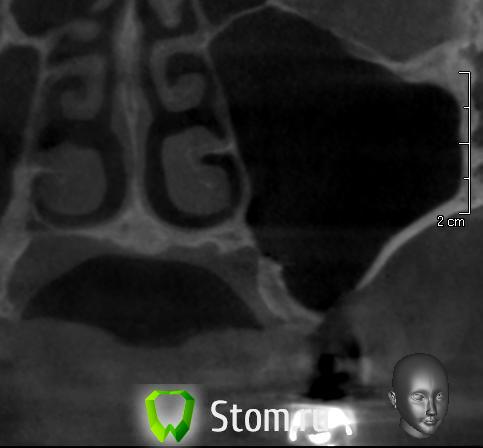

doktorenok Опубликовано 5 декабря, 2011 Поделиться Опубликовано 5 декабря, 2011 Вот чисто теоретически Возможна ли здесь имплантация? Если да, то какова последовательность действий по пластике? Зуб удален год назад, соустье ушито, жалоб никаких не было. Ссылка на комментарий